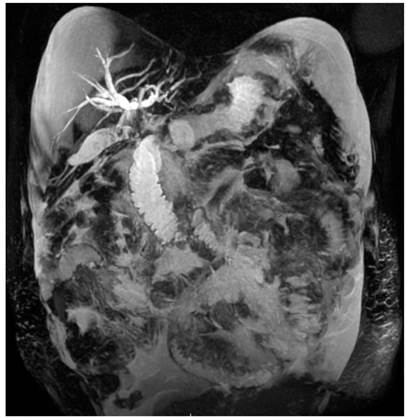

En hospital de remisión requirió manejo con apendicectomía laparoscópica y derivación de vía biliar por colangiopancreatografía retrógrada endoscópica, con inserción de un stent biliar. Hallazgo intraquirúrgico de un plastrón apendicular, abundante líquido peritoneal cetrino, estrechez del conducto hepático común, con sospecha de compromiso neoplásico. Se trasladó al Hospital Militar Central en Bogotá, Colombia, para continuar con manejo integral. Se documentó síndrome biliar obstructivo, con recuento de bilirrubina total de 3,02 mg/dL, bilirrubina directa de 2,71 mg/dL, fosfatasa alcalina de 1006 UI/L, alanina aminotransferasa (ALT) de 149 U/L y aspartato aminotransferasa (AST) de 139 U/L. Los hallazgos de la colangiorresonancia se exponen en la Figura 1 y los de la tomografía axial computarizada (TAC) en la Figura 2. El resultado de la biopsia apendicular evidenció compromiso por adenocarcinoma moderadamente diferenciado de serosa y capa muscular (Figura 3), con inmunohistoquímica positiva para anticuerpos CK7, EMA, CEA monoclonal y CDX2 (Figura 4), que sugirió origen extraapendicular, probablemente de tracto gastrointestinal superior o hepatobiliar.